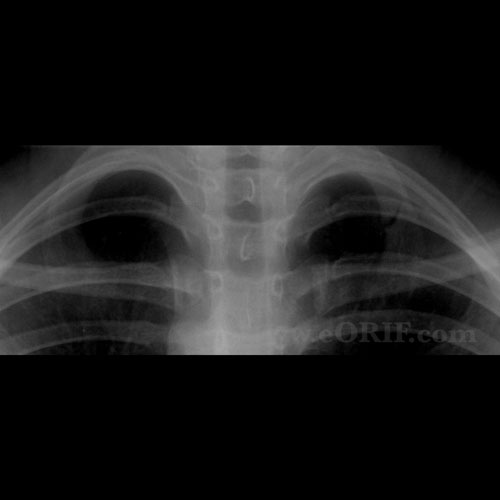

From eorif.com

Rib Stress Fracture Images eORIF Stress Fracture Symptoms Rib People with a stress fracture of a rib commonly complain of increasing chest pain that has developed over a period of weeks. This scan can look for harm to the soft tissues and organs around the ribs. Rib stress fractures usually manifest as a gradual onset of chest or back pain, without a specific mechanism of injury, which may. Signs. Stress Fracture Symptoms Rib.